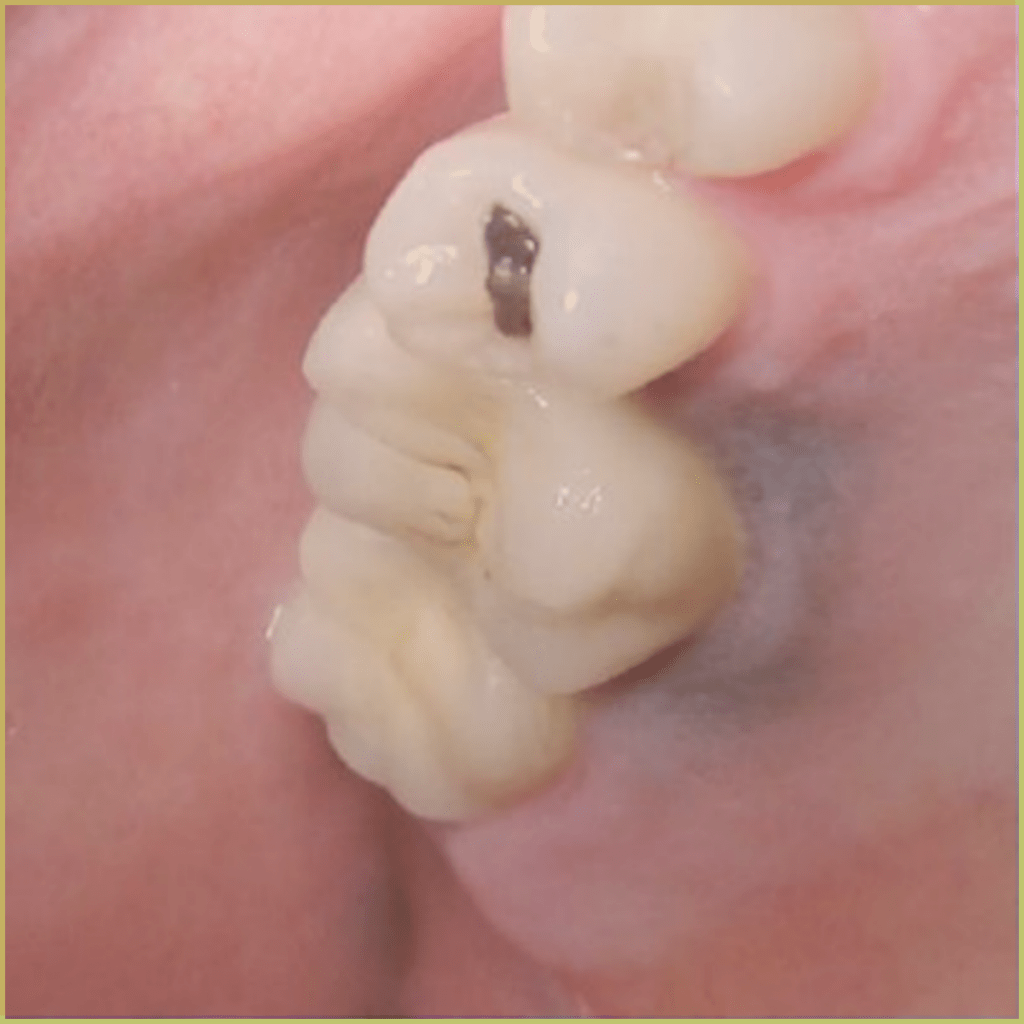

AMALGAM TATTOO

Amalgam Tattoo refers to the discoloration seen in oral tissues where dental amalgam has been deposited. The common clinical presentation includes:

- Well differentiated gray, blue or black focal macule.

- Asymptomatic lesions with no indication of associated inflammation.

- May be visible radiographically.

Diagnosis is based on the lesion history, clinical presentation, and radiographic analysis only. If biopsied, microscopic findings may include:

- Fragments of metal within connective tissue.

- Metal staining of reticulin fibers.

- Particles may be surrounded by fibrous tissue.

- Granulomatous inflammation with a mixture of lymphocytes and plasma cells.

Your differential diagnosis should include:

- Melanoma.

- Vascular malformation.

- Nevus.

- Mucosal melanotic macule.

- Melanoacanthoma.

No treatment is required.